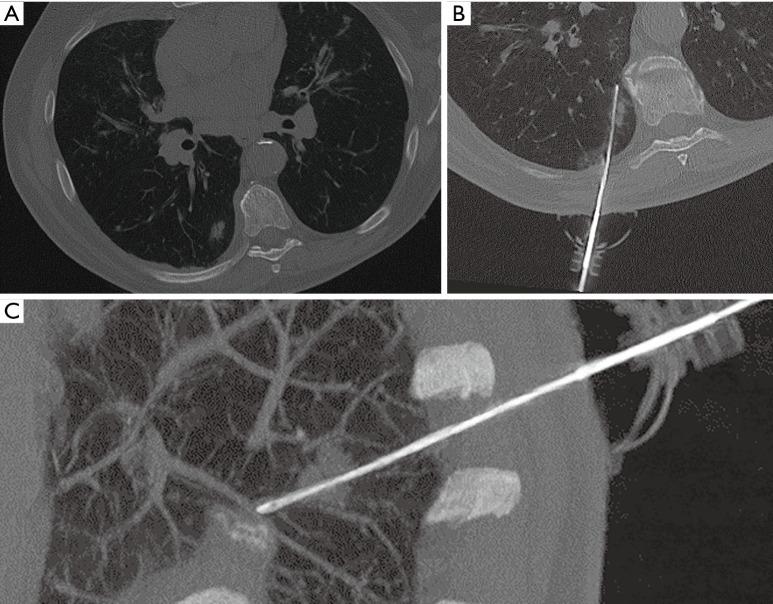

用于经皮CT引导下肺磨玻璃样变活检的增强现实3D导航系统:与标准CT引导技术的比较

Augmented reality 3D navigation system for percutaneous CT-guided pulmonary ground-glass opacity biopsies: a comparison with the standard CT-guided technique.

Augmented reality navigation system for percutaneous computed tomography (CT)-guided pulmonary biopsies has recently been introduced. There are no studies in literature about its use for ground glass lesions biopsies. The aim of this study is to evaluate the effectiveness of an augmented reality infrared navigation system performance on CT-guided percutaneous lung ground glass opacity (GGO) biopsy compared to a standard CT-guided technique.

METHODS

A total of 80 patients with lung GGO who underwent to a percutaneous CT-guided lung biopsy with an augmented reality infrared navigation system were retrospectively enrolled in the study. Comparison was performed with a group of 80 patients who underwent to lung biopsy with the standard CT-guided technique. Evaluation of maximum lesion diameter (MLD), distance between lesion and pleural surface (DPS), distance travelled by the needle (DTP), procedural time, validity of histological sample, procedural complications and the radiation dose to the patient's chest were recorded for each patient of both groups. In addition, each group was divided into two subgroups based on lesion size, according to a cut-off of 1.5 cm (<1.5 cm; ≥1.5 cm).

RESULTS

Augmented reality navigation system showed a significant reduction in procedural time, radiation dose administrated to patients and complications rate compared to a standard CT-guided technique. Technical success was achieved in the 100% of cases in both groups, but the diagnostical success was higher in the group where patients underwent to lung biopsies with the use of navigation system. We also found that using an augmented reality navigation system increases the diagnostical success rate for lesion <1.5 cm. MLD, DPS and DTP did not differ significantly between the two groups of patients.

CONCLUSIONS

The use of an augmented reality navigation system for percutaneous CT-guided pulmonary GGO biopsies has demonstrated a lower incidence of post-procedural complications, a significantly reduction of the radiation dose administered to patients and a higher diagnostical success rate.